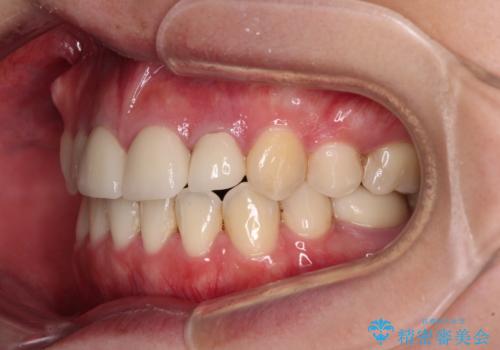

- 八重歯と前歯のデコボコ、開咬を気にして来院された患者様です。

抜歯矯正が必要であることはご自身で理解されており、目立たない装置をご希望であったので、上顎が裏側装置であるハーフリンガル装置にて治療を行うこととしました。

開咬の改善には舌突出癖を改善するためのトレーニングが必要ですが、しっかりと行っていただき、想定よりも早い期間で治療を終えることができました。